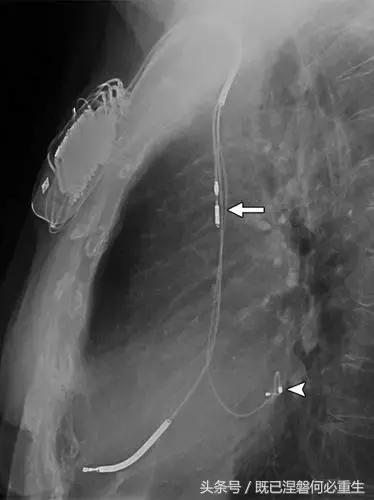

图5AB 在两个不同的患者电极错位和心室穿孔的例子。A,72岁的女性电极错误。 正位(A)和外侧(B)胸部X光片显示圣犹达医学双心室植入式心律转复除颤器与上腔静脉不适当的心房导线位置。 心房导联(箭头,A和B)的尖端高于右心房的水平,并且已经不适当地定位在上腔静脉中。 关注冠状窦引线(箭头B)的正常位置是在侧向投影中右心室(RV)引线的后方。

图5C,70岁女性心室穿孔。 正位胸片显示,圣犹达医疗双室起搏器的RV导联(箭头)超出心室轮廓。 心肌穿孔很少会导致放血或压塞。 患者没有受到并发症或随后的铅改变的不良影响(修订电极显示)。 心室穿孔可能导致对膜片的不适当刺激。